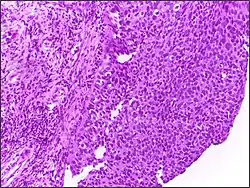

![]() | Tumor giant cell | Malignant neoplasm showing marked anaplasia. Note the marked nuclear pleomorphism, bizarre cells and tumor giant cells. | Category: Histopathology of giant cell tumors | Giant cell tumor |